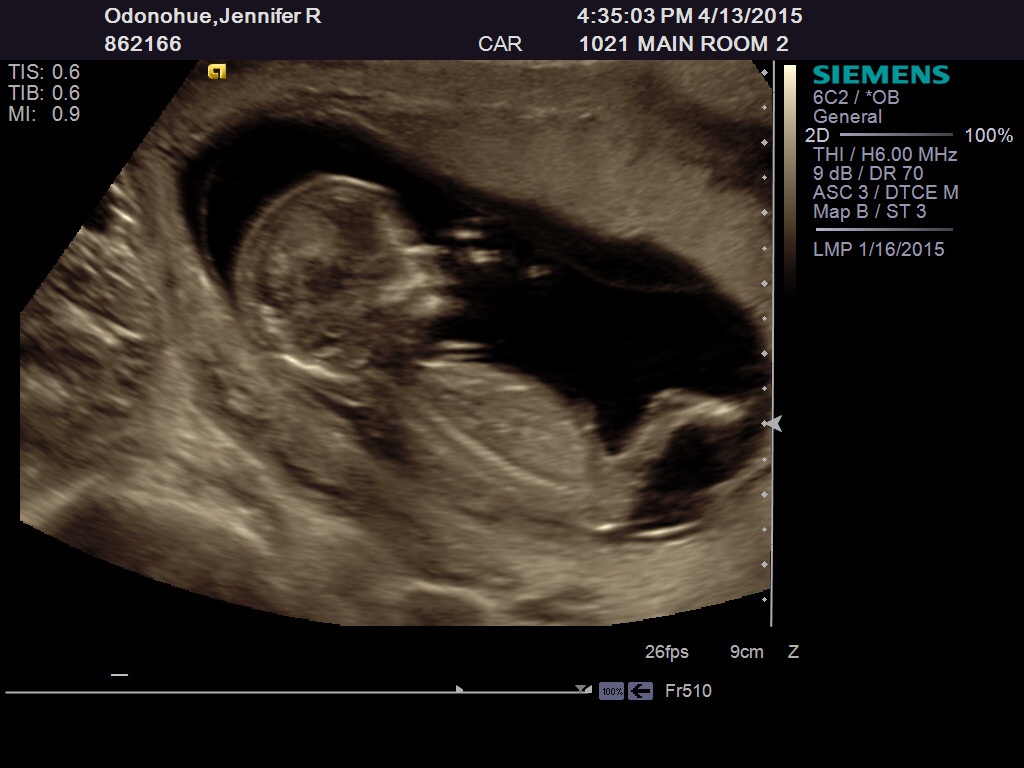

Can't quite make out the nub. Skull looks boyish to me but from what I make out of the nub it looks girlish. 50/50 split

Thinking boy